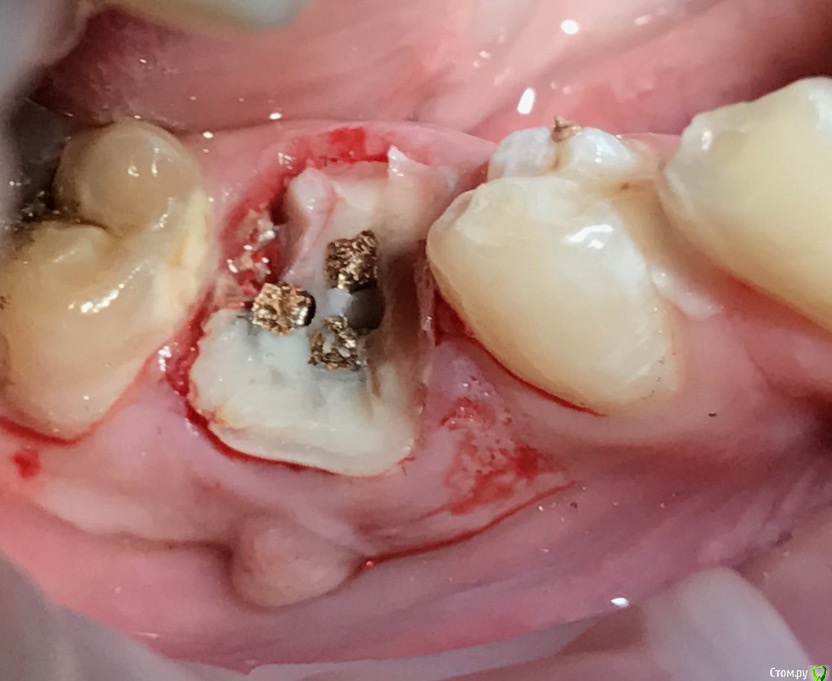

колесников Опубликовано 5 июля, 2019 Автор Поделиться Опубликовано 5 июля, 2019 Ещё раз о ретировалось лоскуте . Из ретромолярной зоны на н/ч перекинут Вестибулярно к 7ке и с неба перекинут Вестибулярно уже для верхней 7ки. Оба случая значительный дефект вестибулярной стенки,одномоментная имплантация,грануляции. Получается хороший стабильный и плотный каркас. 1 зона. 1 Ссылка на комментарий

Дмитрий М Опубликовано 10 июля, 2019 Поделиться Опубликовано 10 июля, 2019 (изменено) спасибо, слежу за вашими работами на фб ) чем прикрыли край импланта? (зеленая стрелка) так понял графт не использовали? Изменено 10 июля, 2019 пользователем Дмитрий М Ссылка на комментарий

колесников Опубликовано 10 июля, 2019 Автор Поделиться Опубликовано 10 июля, 2019 Конечно использовал. Там лохань такая,имплант 5х11 только апексом заякорился. Сверху адгезивная повязка. Ссылка на комментарий

колесников Опубликовано 12 июля, 2019 Автор Поделиться Опубликовано 12 июля, 2019 Жидкий коффердам-если 3-5 дней лунка ушита на формирователь. Жидкотекучий композит-если надо перекрыть на 7-10 дней Ссылка на комментарий